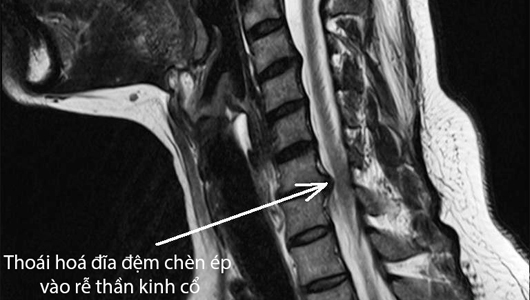

Rách bao xơ đĩa đệm là hiện tượng lớp màng bên ngoài đĩa đệm bị tổn thương, thủng, rách và nhân nhầy tràn ra khỏi vòng sợi, chèn ép lên rễ thần kinh và các đốt sống xung quanh.

Rách bao xơ thuộc giai đoạn thứ 3 của quá trình thoát vị đĩa đệm. Thông thường, người bệnh khó có thể nhận biết tình trạng rách bao xơ này mà cần phải có sự hỗ trợ của xét nghiệm hoặc chụp Xquang, cộng hưởng từ MRI.

Đây được xem là thủ thuật hiện đại và chính xác nhất trong các phương pháp chẩn đoán các bệnh lý liên quan đĩa đệm.

Qua thủ thuật MRI, bác sĩ có thể xác định được vị trí đĩa đệm bị thoát vị, dây thần kinh bị chèn ép.